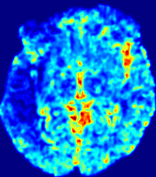

4.3.2 Diffusion Imaging via Advection-Diffusion

Slice #1Slice #2Slice #3Slice #4Slice #5Slice #6Dgtsuperscript𝐷gtD^{\text{gt}}Refer to captionRefer to captionRefer to captionRefer to captionRefer to captionRefer to captionDestsuperscript𝐷estD^{\text{est}}Refer to captionRefer to captionRefer to captionRefer to captionRefer to captionRefer to captionRefer to caption0.300.300.300.240.240.240.180.180.180.120.120.120.060.060.060.000.000.00(mm2/s)𝑚superscript𝑚2𝑠(mm^{2}/s)𝐕est𝟐subscriptnormsuperscript𝐕est2\|\bf{V}^{\text{est}}\|_{2}Refer to captionRefer to captionRefer to captionRefer to captionRefer to captionRefer to captionRefer to caption0.00300.00300.00300.00240.00240.00240.00180.00180.00180.00120.00120.00120.00060.00060.00060.00000.00000.0000(mm/s)𝑚𝑚𝑠(mm/s)

Figure 15: PIANO identifiability testing: diffusion imaging via advection-diffusion. Top row shows Dgtsuperscript𝐷gtD^{\text{gt}} used for simulating ground truth pure diffusion. Rows below show the estimated Destsuperscript𝐷estD^{\text{est}} and 𝐕est2subscriptnormsuperscript𝐕est2\|{\bf{V}}^{\text{est}}\|_{2} on corresponding slices. Note that the plotted value scale for 𝐕est2subscriptnormsuperscript𝐕est2\|{\bf{V}}^{\text{est}}\|_{2} is 0.01 of that for Dgtsuperscript𝐷gtD^{\text{gt}} and Destsuperscript𝐷estD^{\text{est}}.

Similarly, we test the behavior of PIANO when estimating both advection and diffusion from a pure diffusion-driven process. The goal is to determine if PIANO is able to recognize that there is only diffusion governing the given concentration time-series. We use the same ‘Diffusion Imaging’ data simulation of Sec. 4.2.1 as the concentration dataset, PIANO estimates both velocity 𝐕estsuperscript𝐕est{\bf{V}}^{\text{est}} and diffusivity Destsuperscript𝐷estD^{\text{est}}. Estimation results in Fig. 15 confirm PIANO’s identifiability again: the estimated 𝐕est2subscriptnormsuperscript𝐕est2\|{\bf{V}}^{\text{est}}\|_{2} is almost invisible compared to Destsuperscript𝐷estD^{\text{est}}, even plotted with a 1%percent11\% value range compared to that for Destsuperscript𝐷estD^{\text{est}}. On the other hand, Destsuperscript𝐷estD^{\text{est}} achieves comparable estimation performance as ‘Diffusion Imaging via Diffusion’ in which PIANO predicts Destsuperscript𝐷estD^{\text{est}} alone (shown in Fig. 13).